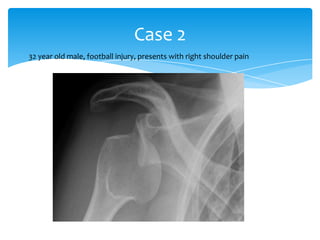

Case 2

32 year old male, football injury, presents with right shoulder pain